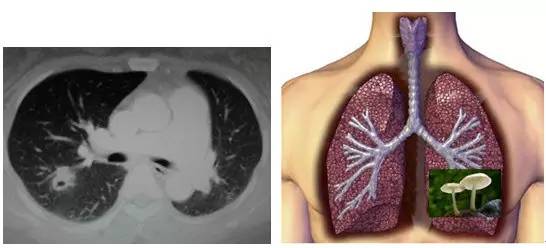

3. 隐球菌感染(「肺里面长蘑菇了」)

这个也像 GGO,还有一个小空洞